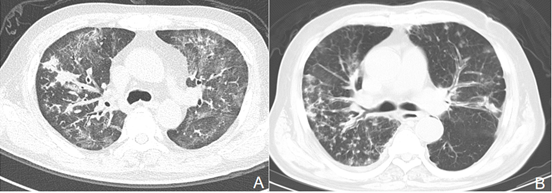

辅助检查:起病1周左右(20181月8日)外院胸部CT出现了明显的纵隔气肿,沿支气管血管束分布的多发结节和斑片影。

图片

转入我科当天行胸部CT检查,距出现症状已2周余,与前相比进展快速,出现大片实变影,原有结节已融合,并且出现空洞。